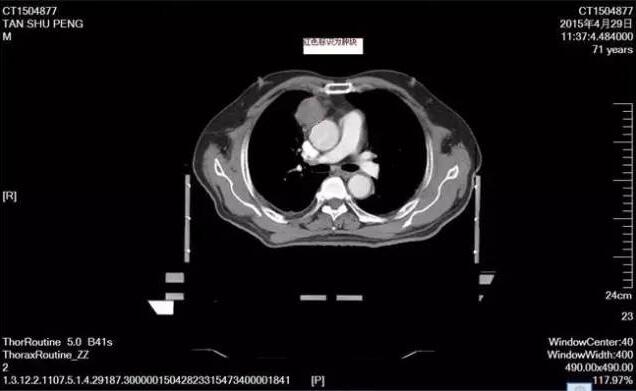

2015年4月,一名七十多歲的老年人因咳嗽咳痰、痰中帶血,被確診為原發(fā)性支氣管肺癌 cT4N2M1 IV期胸膜轉(zhuǎn)移,晚期,建議患者全身化療,患者及家屬考慮年紀較大已經(jīng)七十多歲,全身基礎疾病較多,高血壓病2級,極高危組,冠心病等拒絕化療,4月份只行了單純的放射治療,這是放療前定位的片子:可以見到右前上縱隔結節(jié)狀病灶。